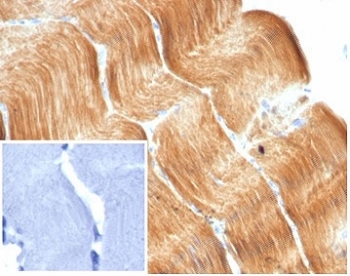

IHC staining of FFPE human skeletal muscle tissue with recombinant Alpha Actinin 2 antibody (clone ACTN2/7040R). Negative control inset: PBS instead of primary antibody to control for secondary binding. HIER: boil tissue sections in pH 9 10mM Tris with 1mM EDTA for 20 min and allow to cool before testing.

IHC staining of FFPE human cardiac muscle with recombinant Alpha Actinin 2 antibody (clone ACTN2/7040R). Negative control inset: PBS used instead of primary antibody to control for secondary Ab binding. HIER: boil tissue sections in pH 9 10mM Tris with 1mM EDTA for 20 min and allow to cool before testing.